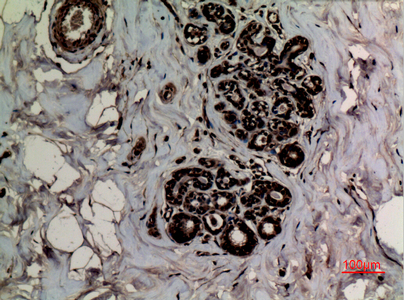

Immunohistochemical analysis of paraffin-embedded human-breast, antibody was diluted at 1:100